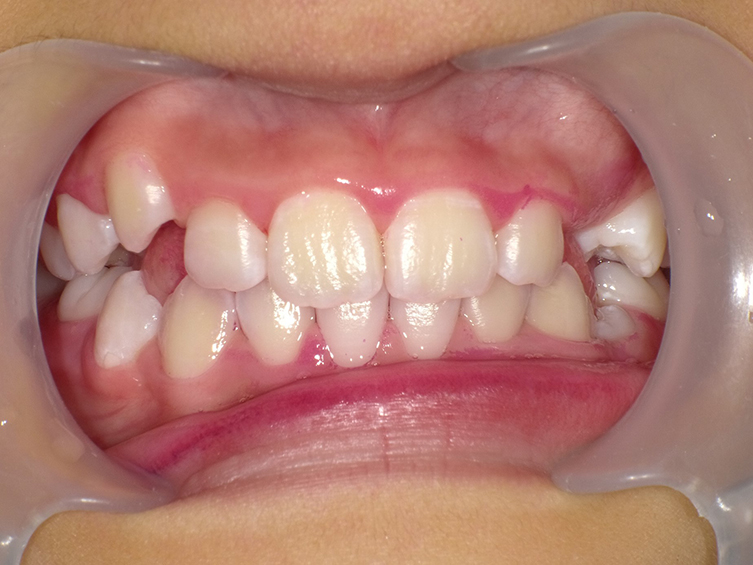

最初の時がこれ

もともと顎が小さく、虫歯のせいで、永久歯もずれ込んでいました。毎日コツコツとプレオルソを使ってくれて……

左上の糸切り歯が最後の難関。この歯もどうにか落ち着いてくれました。

心配していた針金も使わずにすみました。本当によく頑張りましたね。